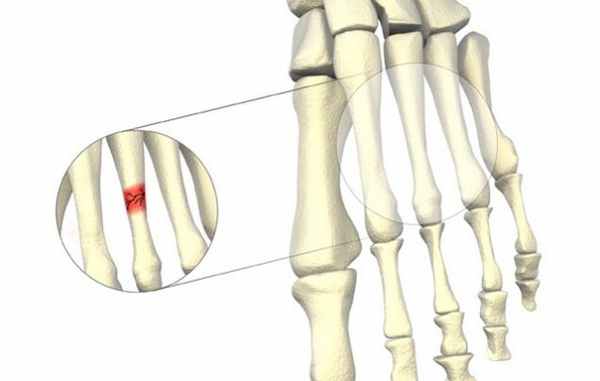

Согласно данным Американской академии хирургов-ортопедов, стресс-переломам наиболее подвержены вторая и третья плюсневые кости стопы, которые тоньше (и часто длиннее), чем соседняя первая плюсневая кость. Именно на эту область идет наибольшая нагрузка во время передвижения при ходьбе или при беге.

По данным хирургов-ортопедов, сильнее других костей стресс-перелому подвержены вторая и третья плюсневые косточки стопы. Область, где они располагаются, сильнее всего задействована в беге. Она отвечает за отталкивание.

Стрессовые переломы происходят в костях, претерпевающих механическую усталость. Они являются следствием чрезмерных повторяющихся субмаксимальных нагрузок, которые создают дисбаланс между костной ресорбцией и формированием. Переломы обычно возникают в месте наибольшей нагрузки; это называют «образованием трещин». Если эту микроскопическую трещину невозможно вылечить и подвергать ее дальнейшим нагрузкам, микроповреждение увеличится, и трещина увеличивается в размерах. Такое увеличение может быть причиной перелома кости на макроскопическом уровне.